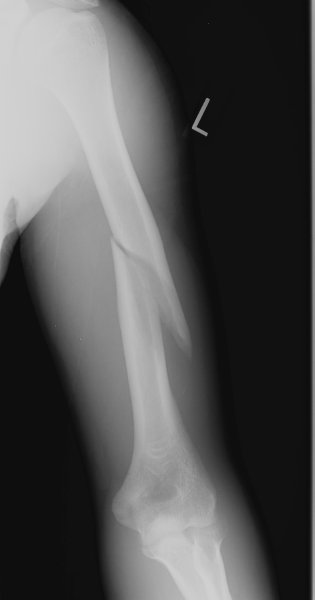

Return to Humeral Shaft Fracture